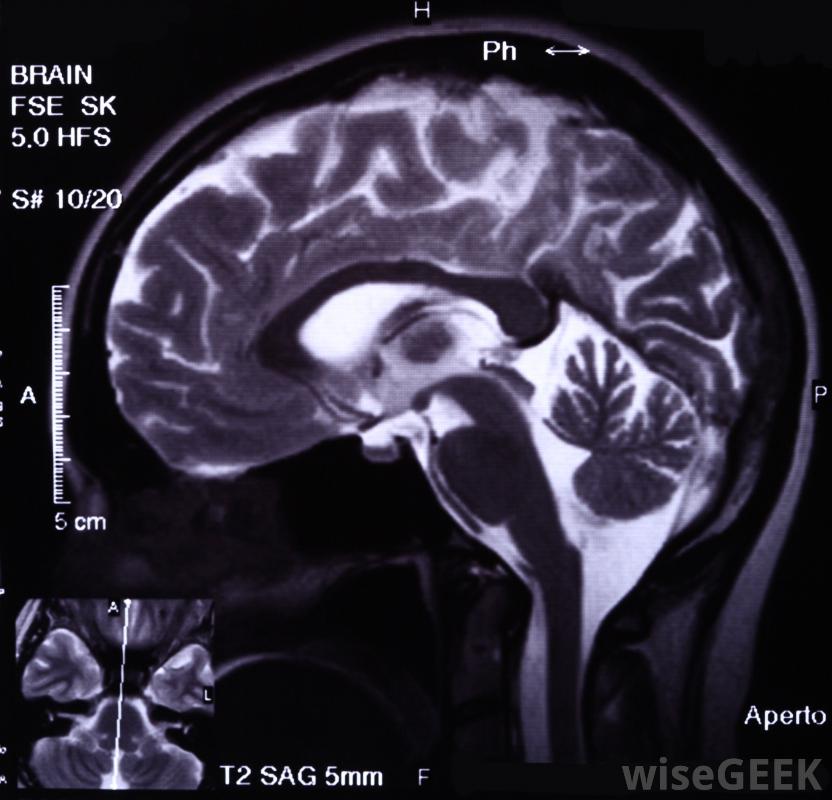

在一些脑成像扫描中可以看到不同的树突模式"树突"一词来源于希腊语中"树"的意思,反映了树突的树状结构,这些结构从细胞体中分支出来,并以微小的延伸高度分枝,每一次伸展都扩大了树突的表面积,确保它不太可能错过来自邻近细胞的信息。

大脑和神经系统发生变化,这是一种被称为可塑性的特征;,允许身体在一生中进化以满足其需求。虽然人们可能认为树枝状结构保持不变,研究表明,事实上,树突会随着时间的推移而发生变化,并会对环境的暗示做出反应。例如,酒精会导致树突萎缩,而学习似乎会使树突变长。人们普遍认为饮酒会损害脑细胞,事实证明,这是正确的,即使它特别伤害树突,而不是整个树突细胞。这些研究显示了大脑和神经系统变化的真实方式,一种被称为可塑性的特性,它允许身体在一生中不断进化以满足自身的需要。神经系统和科学网站。这些图片展示了树突可以采取的许多不同的模式,并展示了这些结构可以随时间变化的方式尤其是来自大脑的图像非常引人入胜。